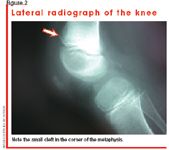

In the following week, the limp persists, as does the pain localized to the right distal femur; no fever or other new systemic symptoms develop. Over the course of the week, the parents relate that their child gradually refuses to walk or bear weight. Repeated radiographs of the lower extremities are normal. Although there is no fever, the orthopedic surgeon is worried about osteomyelitis and orders a bone scan. The bone scan results are normal, essentially making fracture or osteomyelitis very unlikely.